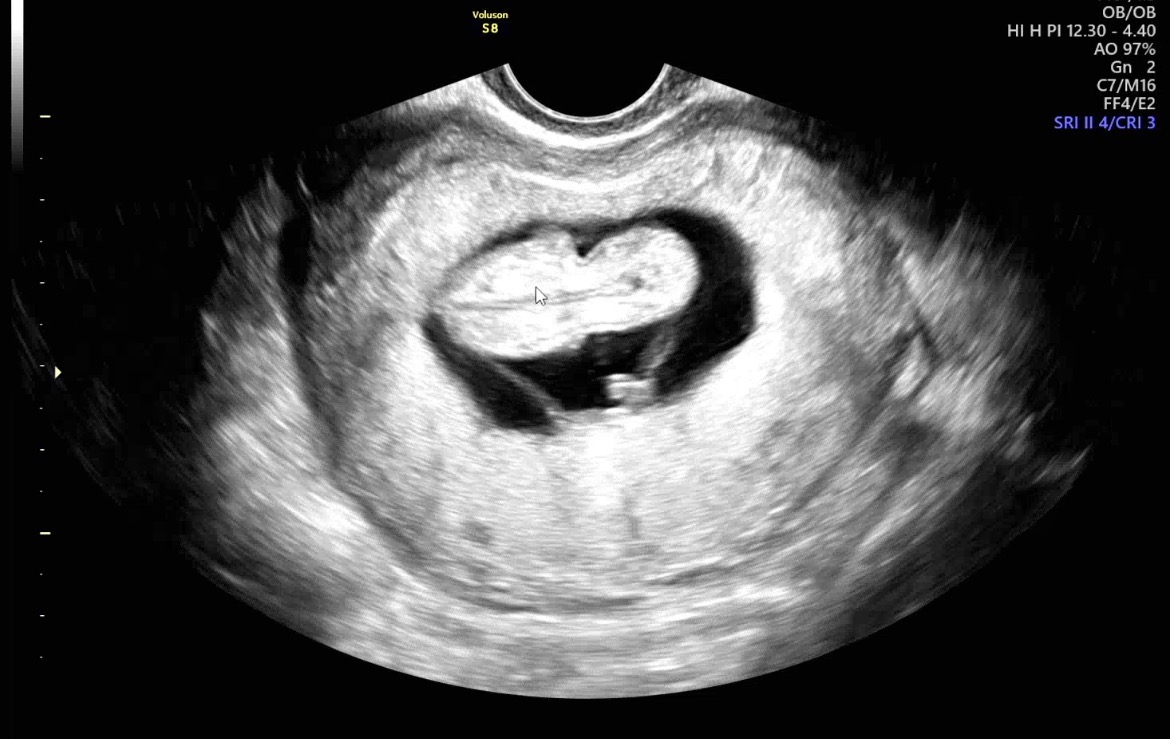

| 가슴 떨리는 임신 이야기를 공유해 주세요. | 이예흔 원장님과 의료진분들 덕분에 기적처럼 첫 번째 시험관 시술로 임신에 성공하게 되어 정말 기쁩니다. 이 소중한 순간은 오래도록 잊지 못할 것 같습니다. |